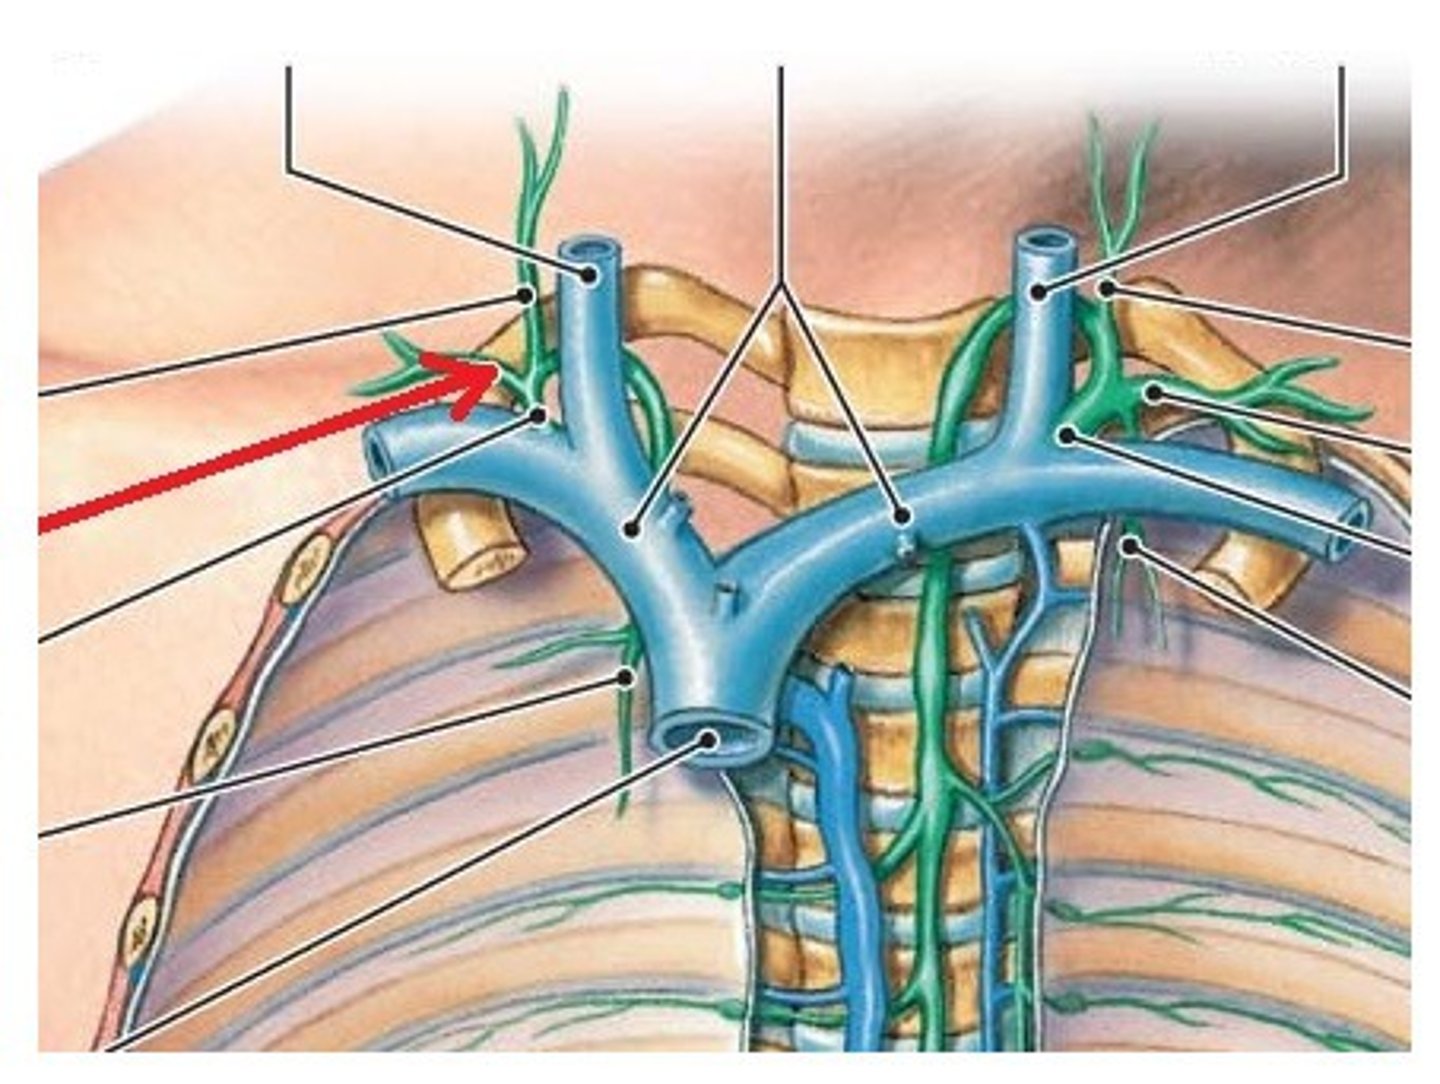

Subclavian trunk

Subclavian vein

Internal jugular vein